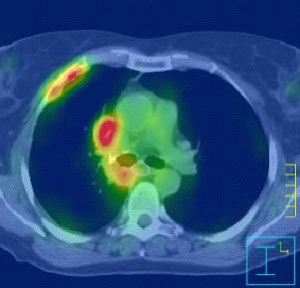

Καρκίνος Πνεύμονα

Η ακτινοχειρουργική με CyberKnife αντιπροσωπεύει μία πανίσχυρη και μεγάλης ακρίβειας τεχνική για ασθενείς με αρχική, υποτροπή ή μεταστατική εντόπιση όγκου στον πνεύμονα. Η θεραπεία είναι ασφαλής να δοθεί σε ασθενείς που δεν μπορούν λόγω άλλων παθολογικών καταστάσεων να χειρουργηθούν και προσφέρει μία πολύ καλή θεραπευτική επιλογή σε ασθενείς με υποτροπιάζουσα ή εμμένουσα νόσο που πριν είχαν ελάχιστες αν όχι καμία, δραστική θεραπεία ικανή να τους βοηθήσει.

Το CyberKnife είναι ένα σύστημα ακτινοθεραπείας που αποτελείται από ένα γραμμικό επιταχυντή τοποθετημένο επάνω σε έναν ρομποτικό βραχίονα.